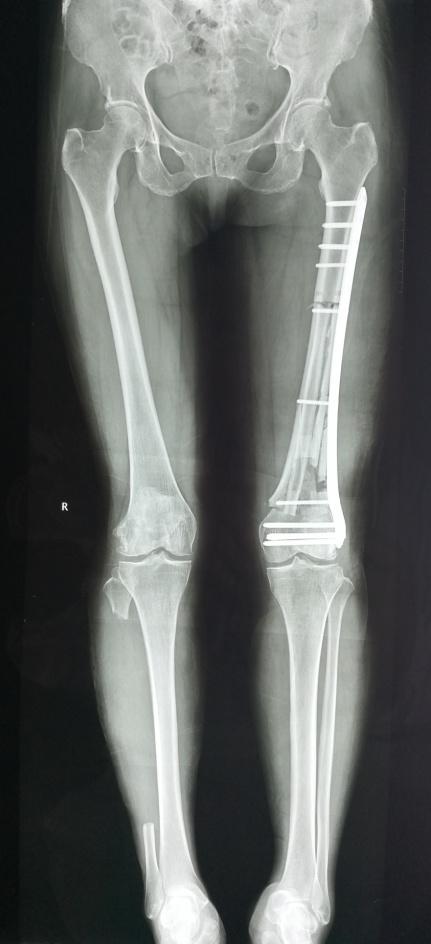

骨病骨肿瘤科近日成功实施“带血管腓骨复合大段异体骨移植手术”。患者冯女士,因左侧大腿疼痛3个月,经检查提示左股骨恶性肿瘤。患者慕名就诊我院骨病骨肿瘤科,科主任胡勇教授团队经反复讨论并细致规划,最后决定为其实施左股骨恶性肿瘤广泛切除,行生物重建手术(即带血管腓骨复合大段异体骨重建股骨),手术过程顺利,患者术后恢复良好康复出院。

胡勇教授指出,对于股骨远端肿瘤切除后的重建问题,目前通常采用金属假体置换来解决,但其术后功能无法媲美原有关节,关节寿命有限,可能面临多次手术翻修等问题。本例手术方案我们保留了患者原有膝关节,采用自体带血管腓骨复合大段异体骨移植重建,达到了生物学重建的标准。